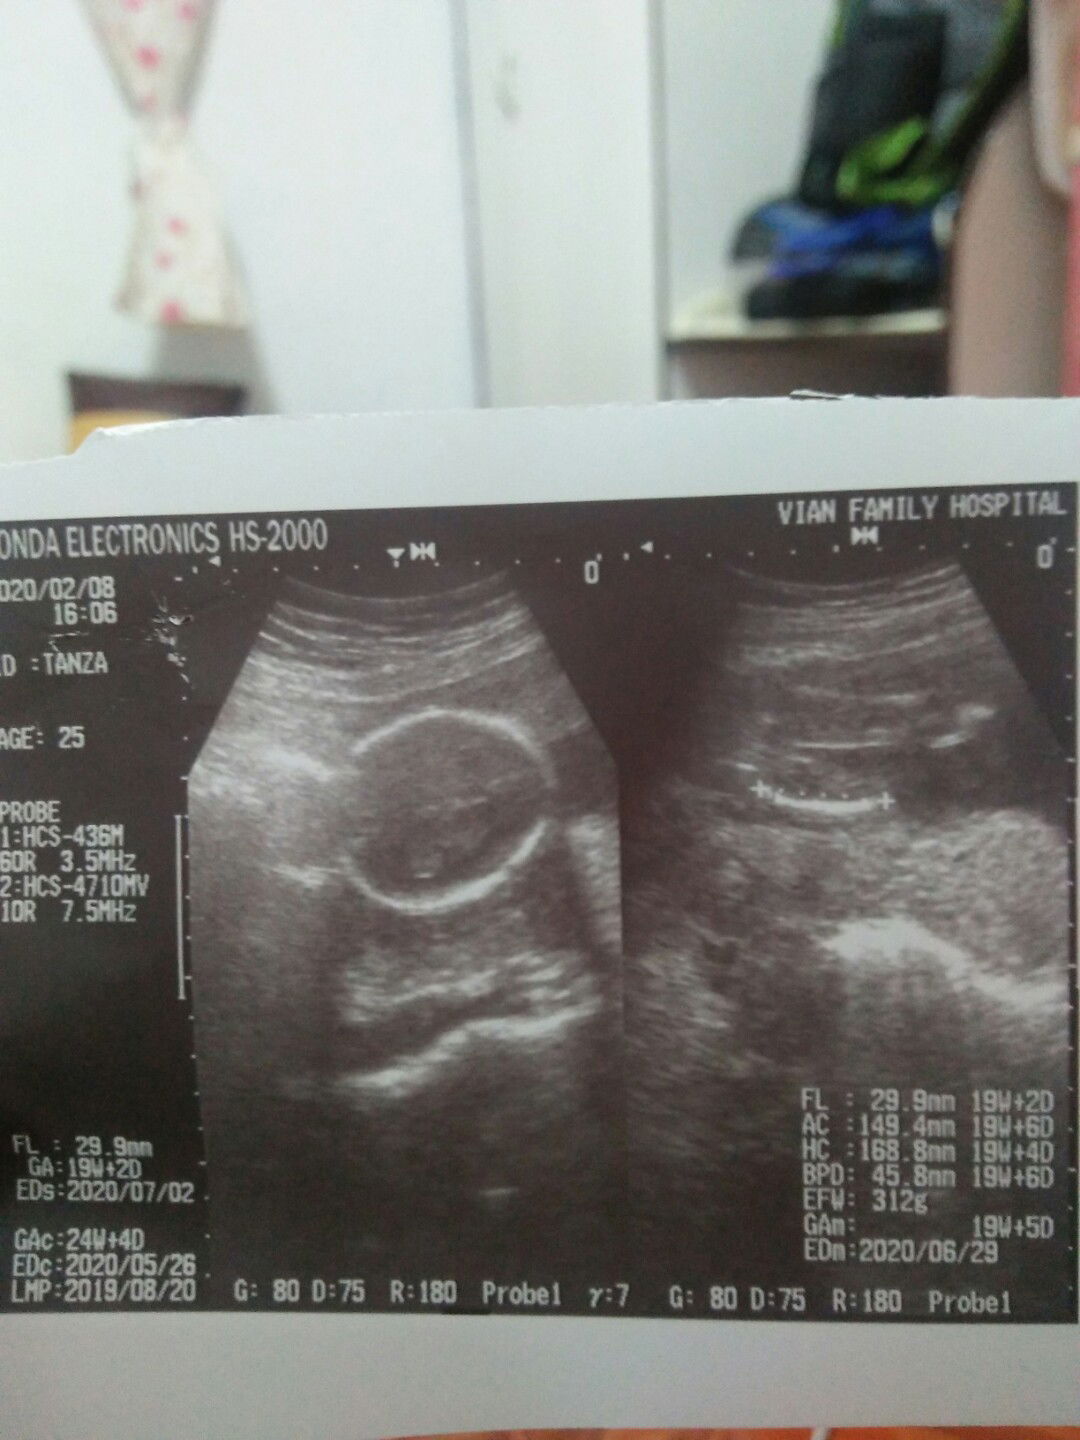

Ok ba ultrasound ng bby ko

ask ko lng

Yes :)